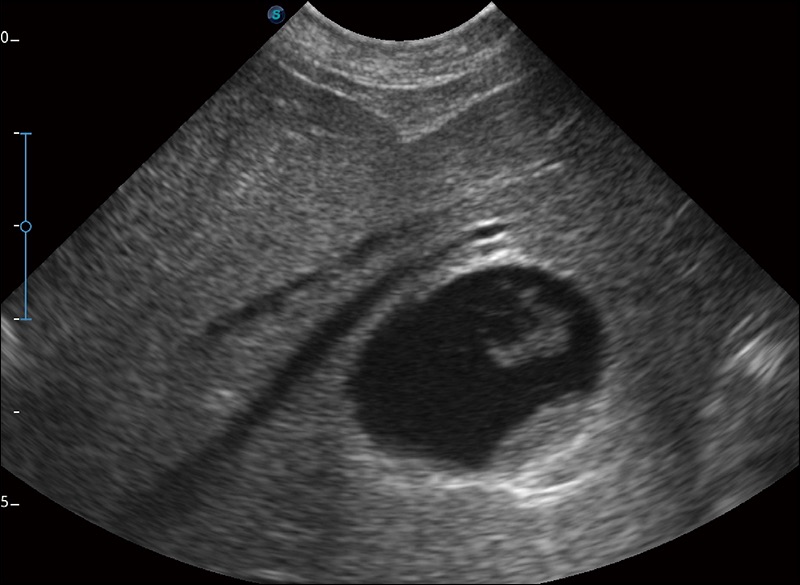

可实时观察感兴趣区域和病变位置